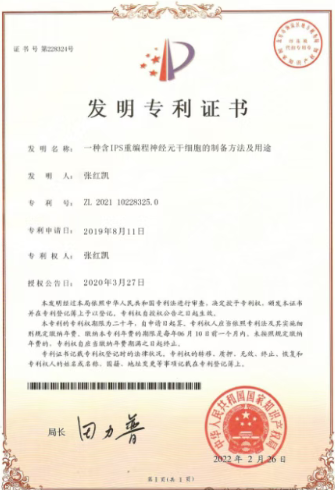

近日,联合国世界生态科学研究院院士、国际细胞康复协会全球总会长张红凯院士领导的科研团队宣布,已成功将诱导多能干细胞(iPS细胞)重新编程为功能完整的神经元干细胞(Neural Stem Cells, NSCs)。

张红凯院士团队开发的这项技术展示了一条全新的神经元干细胞制备路径。研究团队首先从人员干细胞分化成为iPS细胞,随后创新性地将iPS细胞重新编程为功能完整的神经元干细胞。

这种分阶段的重编程策略不仅提高了细胞转化的效率和纯度,还显著降低了成瘤风险,解决了干细胞治疗领域长期面临的安全性问题。

张红凯院士介绍说:“我们的方法避免了传统直接转化可能带来的遗传不稳定问题,分化周期更短,安全性更高,是一种理想的可产业化的种子干细胞制备技术。”